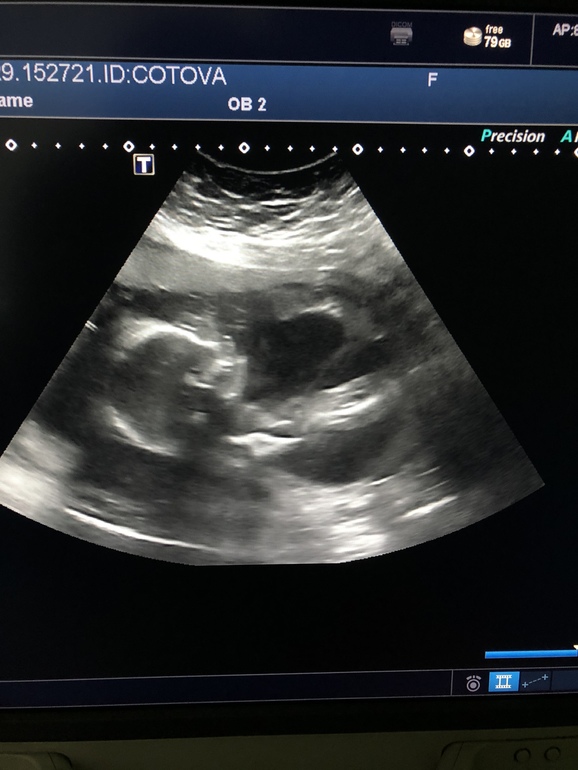

Давайте погадаем, кто у меня в животике?

Снимок размазан, там вообще ничего непонятно кроме головы и тела (видимо аппарат узи старый). На таком сроке становится понятно когда между ног смотрят.

Ну, вот по Вашему фото узи видно профиль и всё. Пол смотрят с другого ракурса.